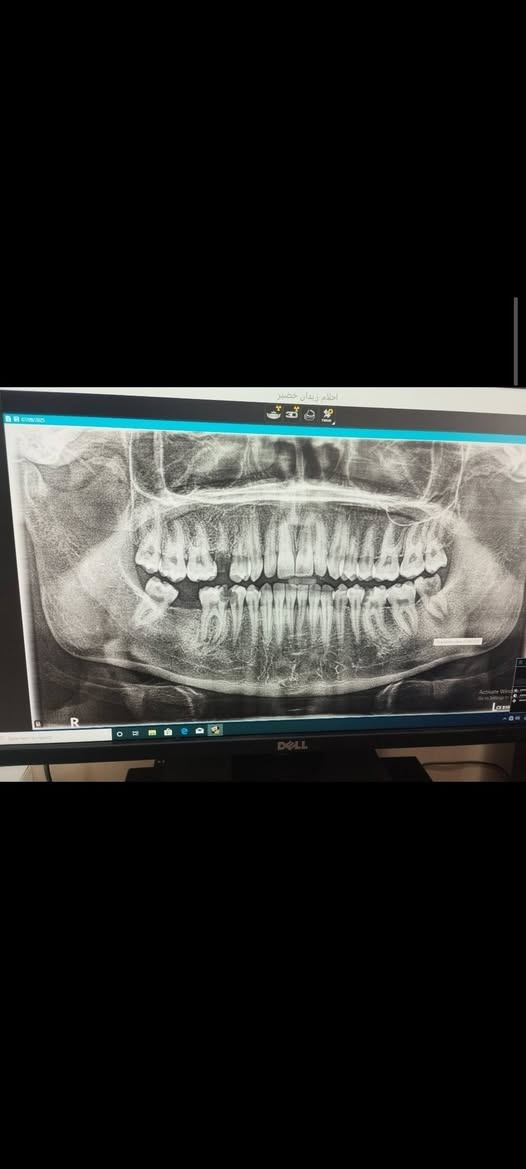

علاج مجاني السلام عليكم ورحمة الله وبركاته للمرضى الاعزاء يتوفر لدينا :- قلع سن. حشوة اعتيادية. تنظيف الاسنان من التكلسات. تبديل حشوة قديمة بحشوة ضوئية. طقم اسنان للفكين الاسفل و الاعلى. مجاني في عيادات جامعة النور التخصصية لطب الاسنان بإشراف الدكاترة المتخصصين في طب الاسنان الاستفسارات والأسئلة العامة الاتصال على الرقم التالي : *********** الدكتور واثق عبدالله حسن ابتسم وانت مرتاح